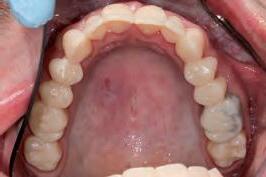

At the laboratory, the dental technician may merge these digitised records using Zirkonzahn.Modifier software (Zirkonzahn Srl; Gais, Italy) to form a precise 3D rendering of the patient’s pre-operative dentofacial situation, with all biomechanical and aesthetic landmarks conveniently available for reference. This offers the technician unparalleled, high-fidelity access to key diagnostic clinical information when compared to conventional analogue-based workflows.4 At this stage, an end goal of prosthodontic treatment may be developed wherein the contours of the proposed restorations are informed on the basis of the patient’s physiognomy, or rather, their unique and characteristic facial features (Figure 4).9 The final proposed design may be fabricated into a snap-on smile try-in, or treatment mock-up, using a flexible machinable polycarbonate (Temp Premium Flexible; Zirkonzahn Srl, Gais, Italy) (Figure 5).

Visualise before you provisionalise

At this early stage of diagnostic work-up, prior to any operative intervention, the clinician and the technician can now communicate to each other and, most importantly, to the patient, in an understandable visual rhetoric, a precise end goal of treatment from which a meeting of the minds may be achieved (Figures 6 and 7).5

FIGURE

FIGURE 6: Prior to any irreversible and biologically expensive operative intervention, the tripartite stakeholders (patient, clinician and dental technician) of the reconstruction can achieve a precise meeting of the minds in a universally understandable visual rhetoric regarding the intended end goal of treatment.

FIGURE 7: Close-up extra-oral and intra-oral views illustrating satisfying contours of a proposed definitive restoration.